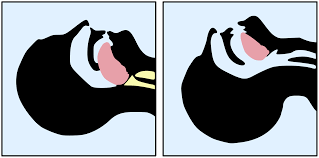

Suction-Assisted Containment of Respiratory Droplets During Airway Management With the SALAD Technique For more information: bit.ly/34dJUI9 #ICAS20 #surgery #anesthesia #anesthesiaconference #surgeryconference cr: anesthesiologynews